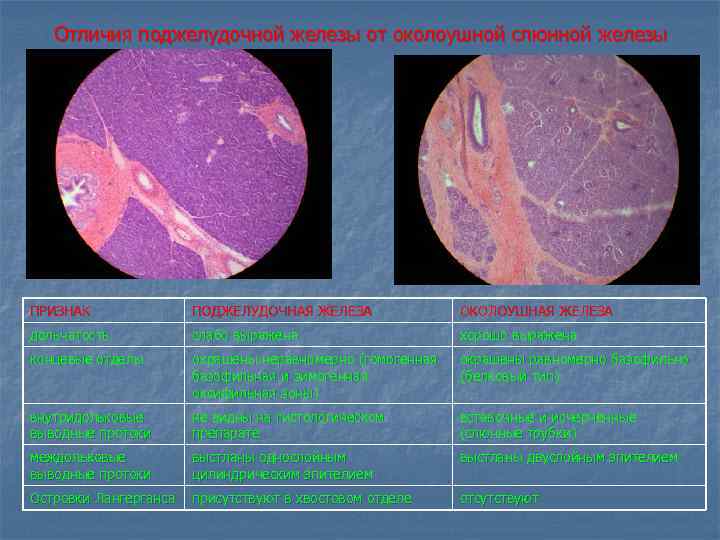

Отличия поджелудочной железы от околоушной слюнной железы ПРИЗНАК ПОДЖЕЛУДОЧНАЯ ЖЕЛЕЗА ОКОЛОУШНАЯ ЖЕЛЕЗА дольчатость слабо выражена хорошо выражена концевые отделы окрашены неравномерно (гомогенная базофильная и зимогенная оксифильная зоны) окрашены равномерно базофильно (белковый тип) внутридольковые выводные протоки не видны на гистологическом препарате вставочные и исчерченные (слюнные трубки) междольковые выводные протоки выстланы однослойным цилиндрическим эпителием выстланы двуслойным эпителием Островки Лангерганса присутствуют в хвостовом отделе отсутствуют